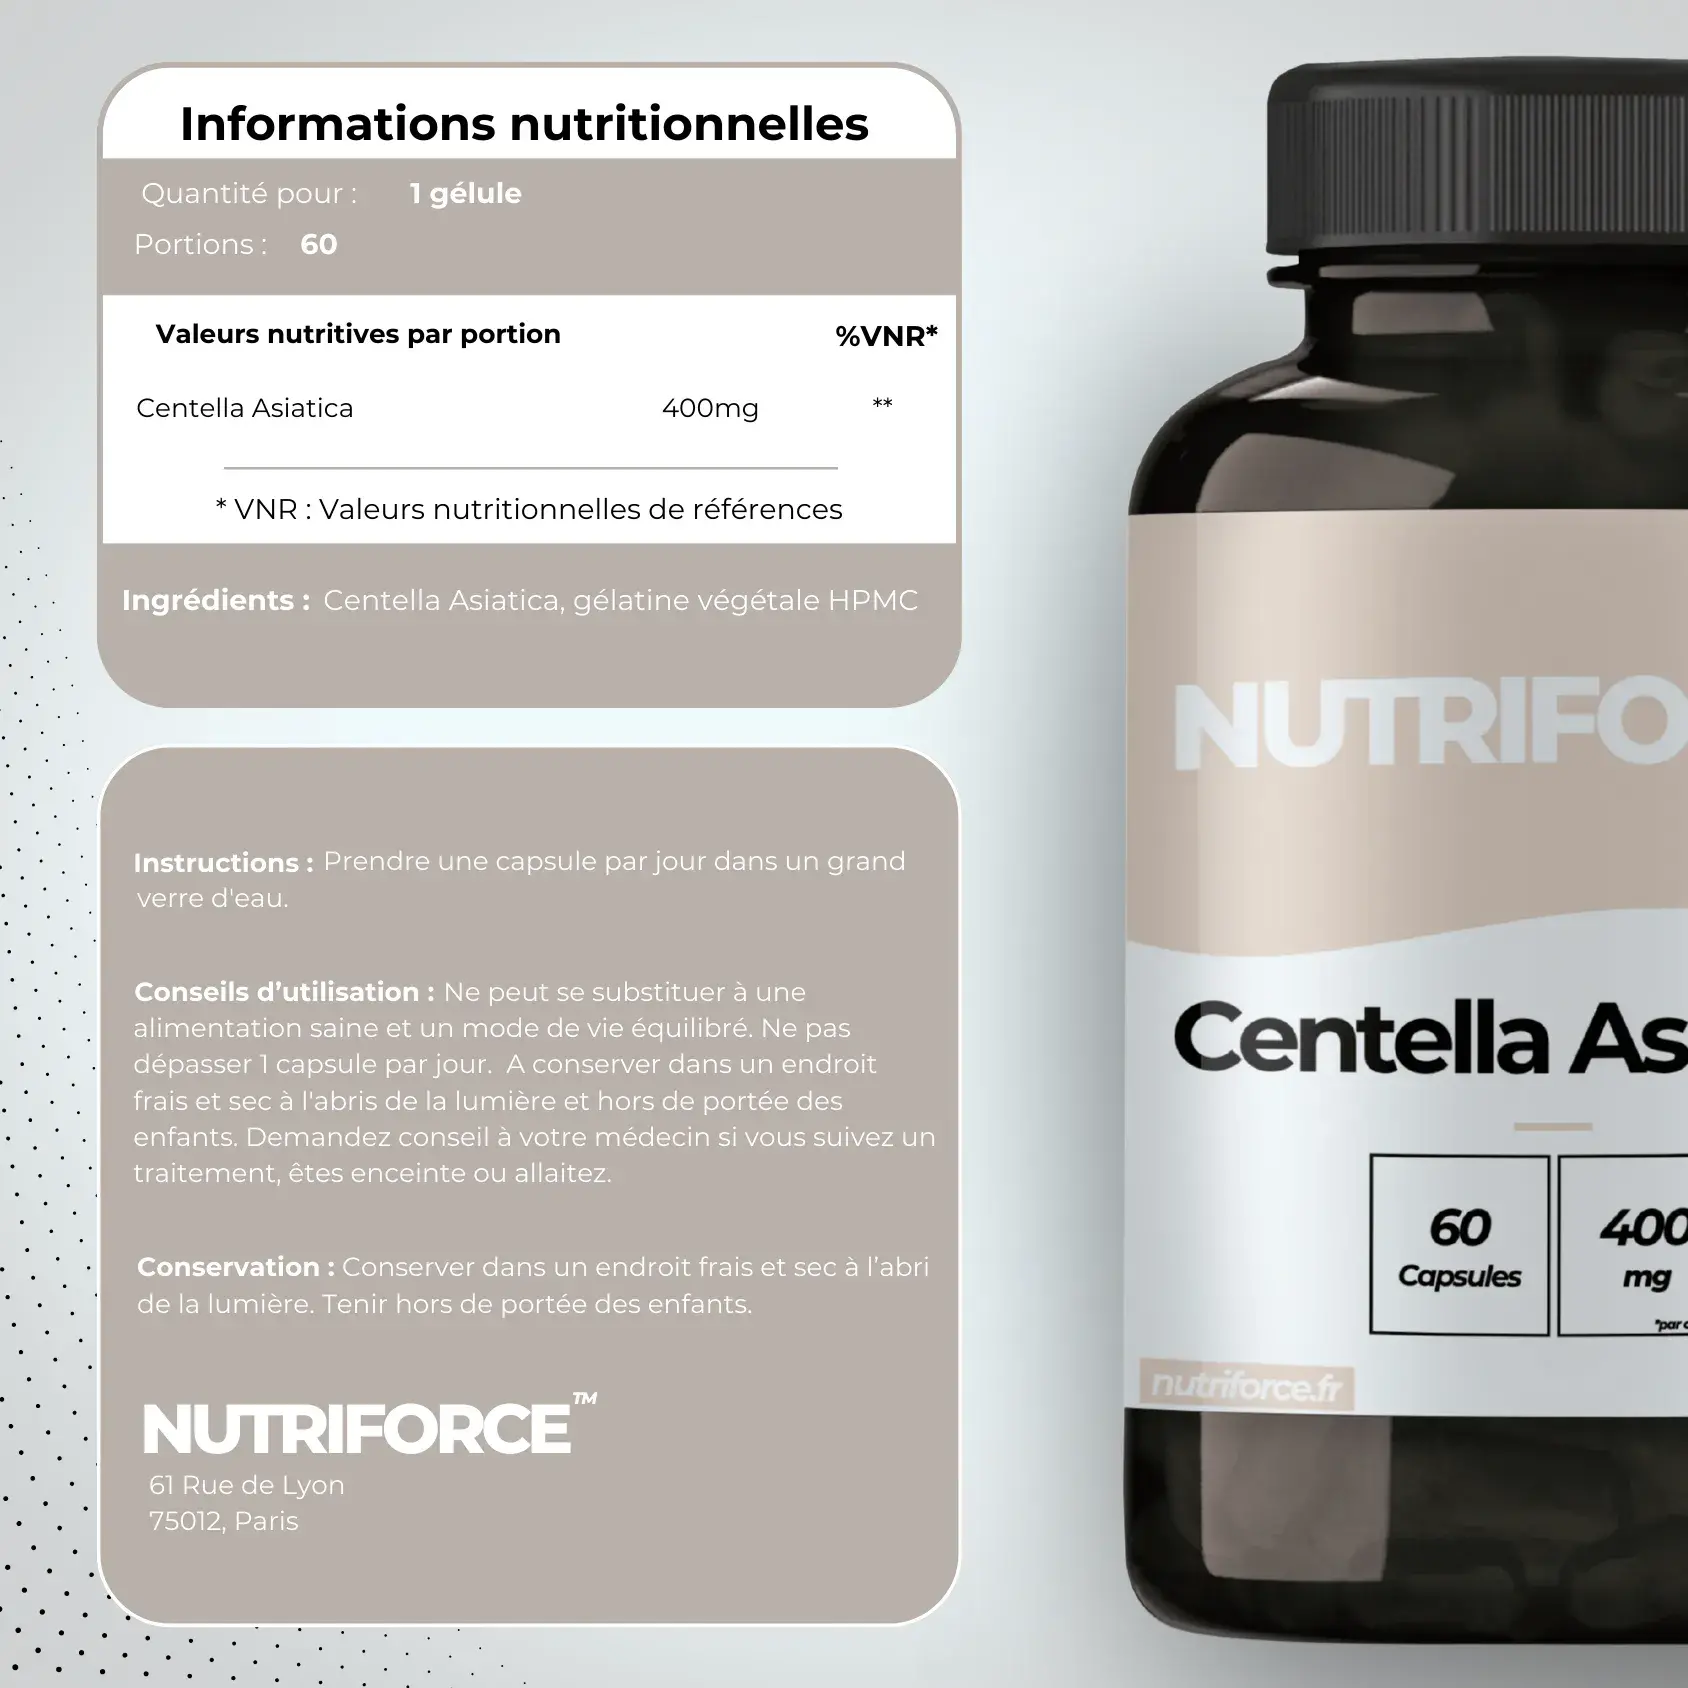

Amélioration de la santé de la peau

La Centella Asiatica est un complément alimentaire très intéressant pour améliorer la santé de la peau, elle stimule la production de collagène, favorise la cicatrisation des plaies, réduit les cicatrices et améliore l’apparence générale de la peau.

Elle est également utilisée pour traiter les problèmes de peau tels que l’eczéma et le psoriasis ou la dermite séborrhéique.

La Centella Asiatica a des propriétés anti-inflammatoires

La Centella Asiatica est connue pour ses propriétés anti-inflammatoires.

Elle est utilisée pour traiter certaines inflammations comme l’arthrite, les tendinites et douleurs articulaires ainsi que les conditions inflammatoires de la peau.

Un soutien cognitif puissant

Des études montrent que la centella asiatica a un effet bénéfique sur la santé cognitive. Il s’agit d’un complément très efficace pour améliorer la mémoire et le fonctionnement du cerveau.

Elle aide aussi à réduire l’anxiété et le stress pour favoriser naturellement le bien-être.

La centella asiatica améliore la circulation sanguine et lymphatique

La centella asiatica aide à renforcer les vaisseaux sanguins et à améliorer la circulation sanguine.

Une raison de plus pour laquelle elle est utilisée contre les rougeurs de peau. Elle favorise également la circulation lymphatique, ce qui permet le drainage des toxines et des déchets du corps.

La centella asiatica contribue ainsi à une meilleure santé grâce à l’amélioration du système lymphatique et cardiovasculaire.

Un anti-oxydant naturel

La centella asiatica est riche en composés antioxydants puissants qui aident à neutraliser les radicaux libres dans le corps.

Elle permet de réduire le vieillissement et de protéger les cellules contre les dommages oxydatifs liés au passage du temps.